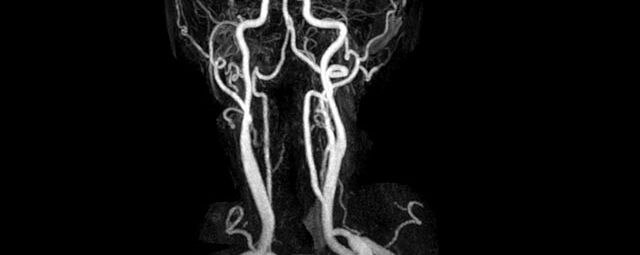

Halsgefäße

• intrakranielle Gefäße (Abklärung Verschluss, Stenose, Aneurysma)

• Halsgefäße zur Therapieplanung (z.B. Stent, Operation)